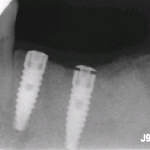

Pomocí zubních implatátů lze nahradit jednotlivé zuby i skupiny zubů. Implantát je kovový váleček z titanu, který má závit jako šroub. Ten je poté zaveden na místo zubního kořene do kosti čelisti.

Po vhojení implantátu do kosti je implantát vybaven nadstavbou, na kterou se vymodeluje v našem případě keramická korunka zubu.